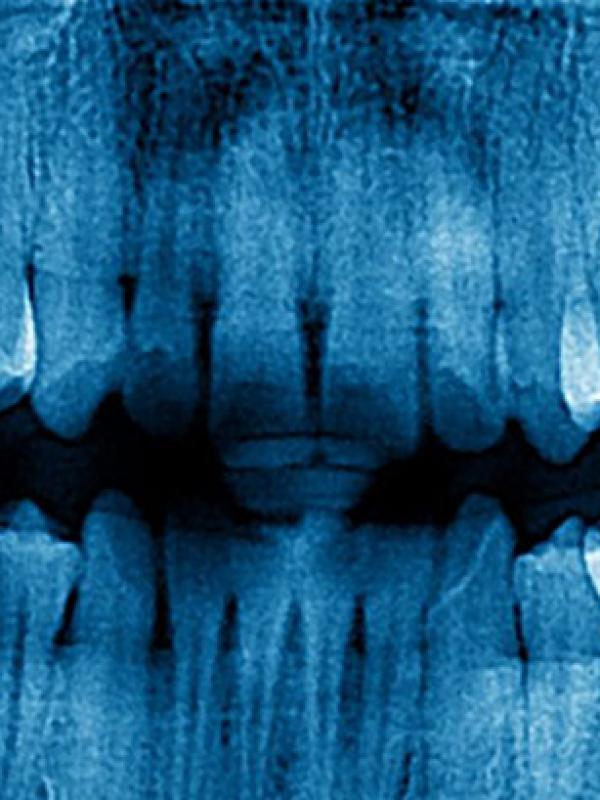

Professional doctorate in dentistry with IRIMC No.36452, with years of experience in providing various dental services. with numerous domestic and international specialized certificates.